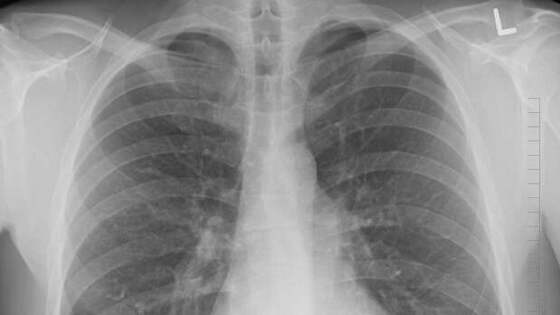

По имеющимся данным, в одной из школ Волгоградской области проводили проверку учеников, собирая пробы Манту. 13-летнего подростка отправили на консультацию к фтизиатру. Последующий рентген и КТ-исследование выявили у него кисту легкого.

Мальчику провели экстренную операцию, в которой участвовали заведующий кафедрой детской хирургии ВолгГМУ Дмитрий Андреев и детский хирург клинической больницы скорой медпомощи №7 Октай Дамиров. Операция длилась 1,5 часа, кисту удалось удалить. В данный момент здоровью и жизни мальчика ничего не угрожает.